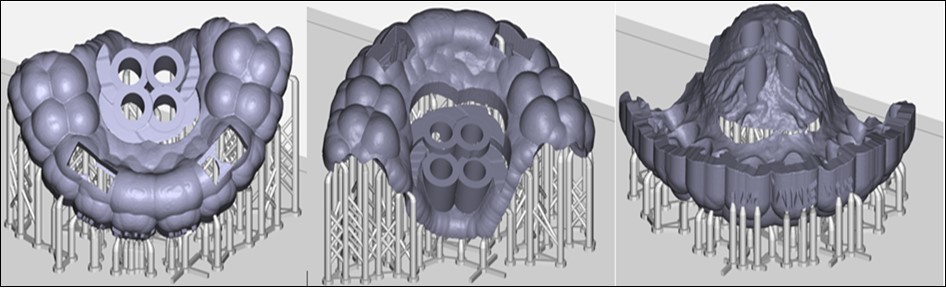

After this stage, this file was exported in RayWare software (Figure 7) and printed using a autoclavable resin (Surgical Guide-MoonRay).

Figure 7.Final preview of the surgical guide before printing